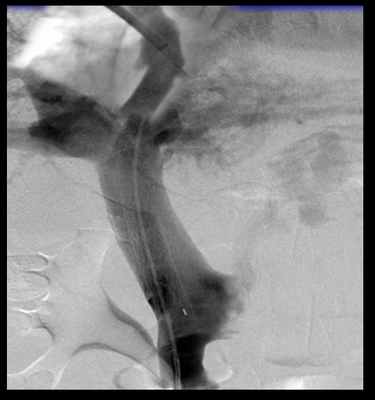

При выполнении TIPS крайне важны правильная регистрация и интерпретация показателей венозного давления. Измерение ГДПВ обычно проводится под седацией и местной анестезией. Интродьюсер устанавливается обычно в правую яремную вену пункционно по методике Сельдингера. Реже используются бедренный или кубитальный доступы. Катетер с баллончиком на рабочей части (Swan-Ganz или Goodale Lubin) диаметром 7-Fr под рентген-телевизионным контролем проводится и «заякоривается» в печеночной вене на глубине 3–4 см от устья печеночной вены. Измеряется СДПВ. После стабилизации показателей СДПВ и подтверждения герметичности окклюзии просвета печеночной вены баллоном трехкратно регистрируются показатели ДЗПВ. Учитывается их среднее значение, причем разница всех трех измерений не должна превышать 1 мм рт. ст. При наличии показаний к шунтированию проводник из печеночных вен через паренхиму печени низводится в одну из ветвей воротной вены. Проводятся канюляция воротной вены и портография. Устанавливается саморасширяющийся стент.

Трансюгулярное внутрипеченочное портосистемное стентирование (TIPS) представляет собой эндоваскулярную операцию по созданию искусственного канала в печени, который обеспечивает отток крови из воротной вены в нижнюю полую вену, минуя пораженную печеночную ткань.

Операция эффективно останавливает кровотечения из варикозных вен пищевода и уменьшает асцит, за счет снижения давления в воротной вене, которое всегда повышено при циррозе печени.

Операция проводится в рентгеноперационной под контролем ангиографии. Во время вмшетельства используются контрастные вещества и ультразвуковое сканирование печени. Средняя продолжительность вмешательства около 2 часов.

Трансюгулярное внутрипеченочное портосистемное шунтирование проводится под рентгеноскопическим контролем с использованием ультразвукового сканирования для контроля доступов к сосудам.

Доступ к печеночной вене осуществляется через внутреннюю яремную вену на шее. Для облегчения доступа используется ультразвуковой контроль. После пункции устанавливается проводник и интродьюсер. Проводник с катетером проводятся в нижнюю полую и печеночную вену. После установки катетера в печеночной вене измеряется давление прямым методом, чтобы рассчитать в последующем градиент.

Для поиска ветви воротной вены может использоваться УЗИ навигация, либо проводится пункция печени под УЗИ контролем и проводится контрастное исследование портальной системы с использованием функции roadmap.

После определения целевой воротной вены через катетер в печеночной вене проводится пункция специальной иглой. Проведя последнюю в воротную вену через нее устанавливают проводник и проводят катетер. Проводится контрастирование воротной системы через яремный катетер и замеряется давление в воротной системе.

Через паренхиму печени по проводнику проводится баллон, который затем раздувается создавая канал в печеночной ткани. После извлечения баллона по проводнику проводится специальный стент-графт, представляющий собой трубчатую металлическую сетку покрытую внутри специальным герметичным пластиком.

Таким образом, мы соединяем прямым шунтом воротную и печеночную вену, что способствует снижению давления в воротной системе и предупреждает рецидивы кровотечения.